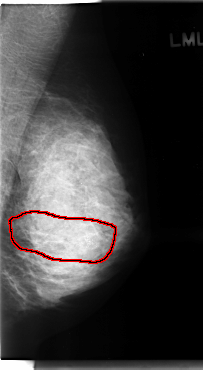

C_0120_1.LEFT_CC

LEFT_CC LINES 4824 PIXELS_PER_LINE 2632 BITS_PER_PIXEL 12 RESOLUTION 50 OVERLAY

FILE: C_0120_1.LEFT_CC.OVERLAY

TOTAL_ABNORMALITIES 1

ABNORMALITY 1

LESION_TYPE CALCIFICATION TYPE AMORPHOUS-PLEOMORPHIC DISTRIBUTION SEGMENTAL

ASSESSMENT 5

SUBTLETY 5

PATHOLOGY MALIGNANT

TOTAL_OUTLINES 1

BOUNDARY